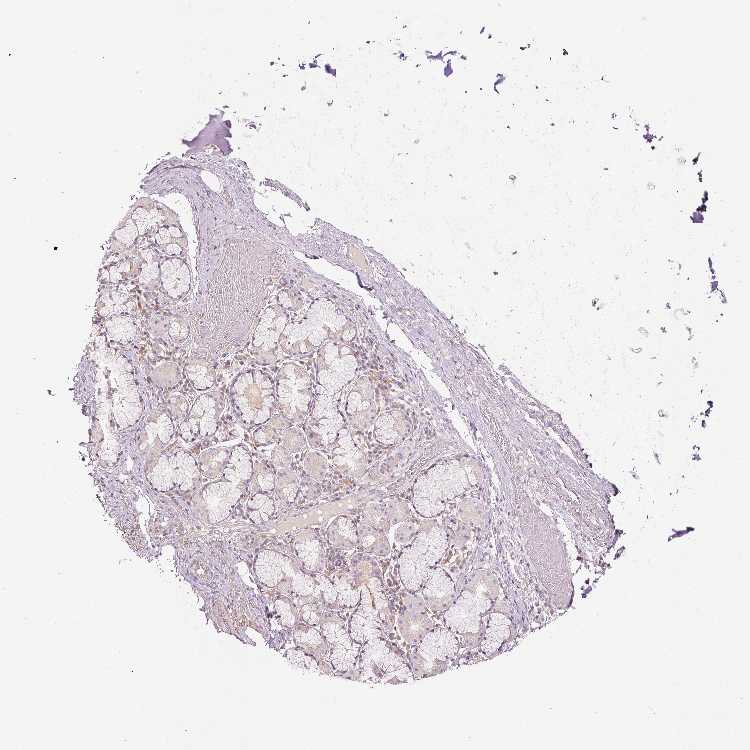

ADIPOSE TISSUE - Antibody stainingi

Antibody staining in the annotated cell types in the current human tissue is reported as not detected, low, medium, or high, based on conventional immunohistochemistry profiling in selected tissues. This score is based on the combination of the staining intensity and fraction of stained cells.

Each image is clickable and will lead to virtual microscopy that enables deeper exploration of all samples and also displays staining intensity scores, fraction scores and subcellular localization as well as patient and tissue information for each sample.

Antibody HPA049810

Adipocytes Not detected